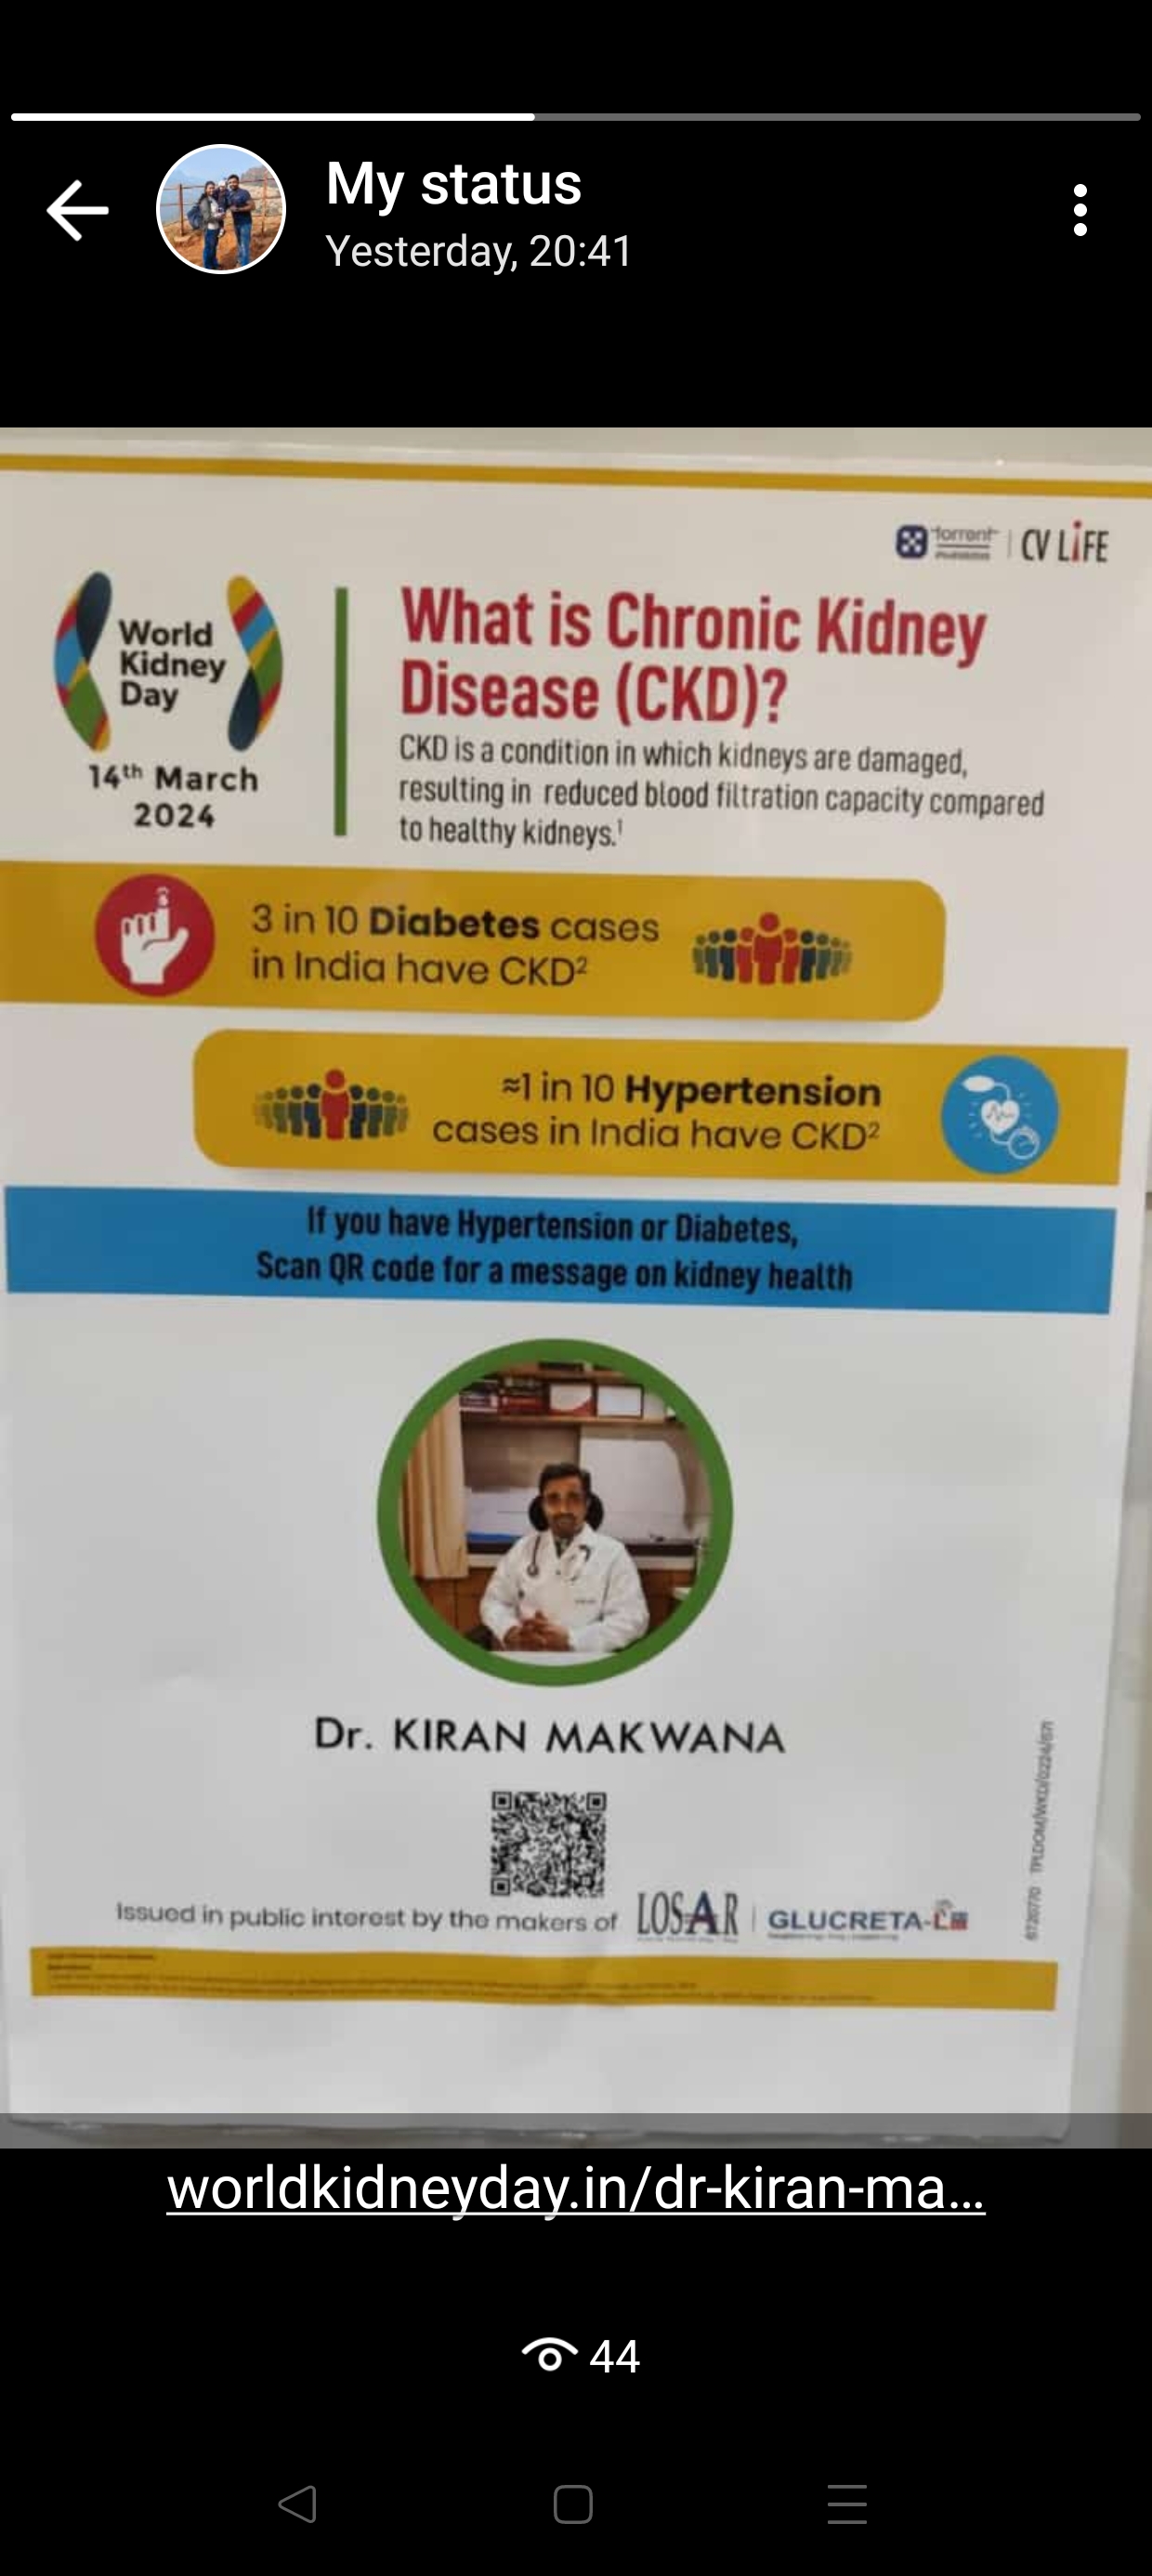

Aum clinic provide pediatric to geriatric care along with basic surgical dressing and Management of infectious disease as well as non communicable chronic diseases like Hypertension , diabetes , arthritis and thyroid . we also have dental department to deal with all dental issues.